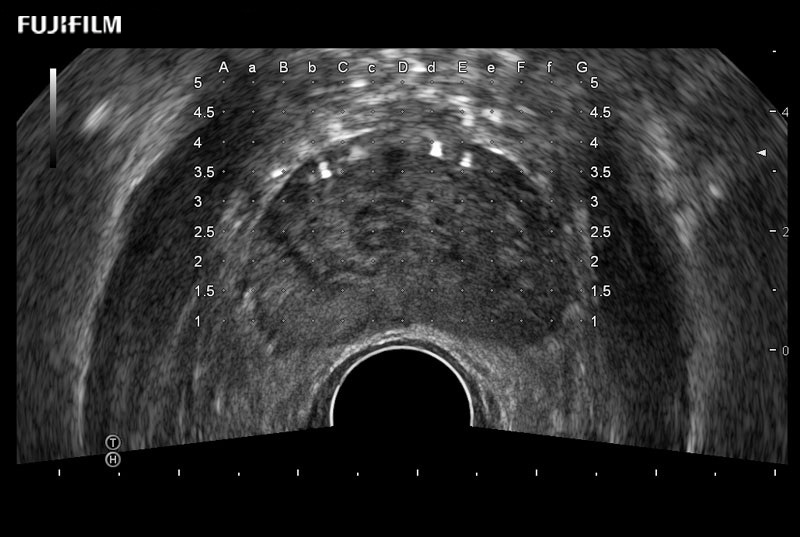

Exclusive 200° FOV end-fire prostate biopsy transducer.

Main Specifications:

Provides real-time imaging of both the sagittal and transverse planes